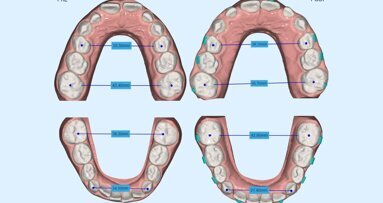

Confronto prima e dopo il trattamento (Figg. 10a-10d)

Figg. 10a, 10b_Foto extraorali ed intraorali di inizio trattamento. Il sorriso iniziale della paziente non permetteva una eccessiva intrusione degli incisivi superiori ma, nonostante questo, risulta migliorato il display dentale e l’ampiezza del sorriso.

Figg. 10a, 10b_Foto extraorali ed intraorali di inizio trattamento. Il sorriso iniziale della paziente non permetteva una eccessiva intrusione degli incisivi superiori ma, nonostante questo, risulta migliorato il display dentale e l’ampiezza del sorriso.

Figg. 10c, 10d_Foto extraorali ed intraorali di fine trattamento.

Figg. 10c, 10d_Foto extraorali ed intraorali di fine trattamento.